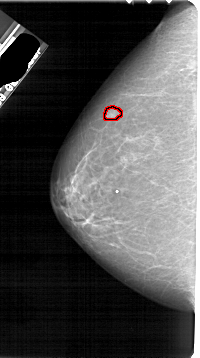

A_1884_1.LEFT_MLO

LEFT_MLO LINES 5461 PIXELS_PER_LINE 2971 BITS_PER_PIXEL 12 RESOLUTION 43.5 OVERLAY

FILE: A_1884_1.LEFT_MLO.OVERLAY

TOTAL_ABNORMALITIES 1

ABNORMALITY 1

LESION_TYPE MASS SHAPE LOBULATED MARGINS OBSCURED

ASSESSMENT 4

SUBTLETY 3

PATHOLOGY BENIGN

TOTAL_OUTLINES 1

BOUNDARY